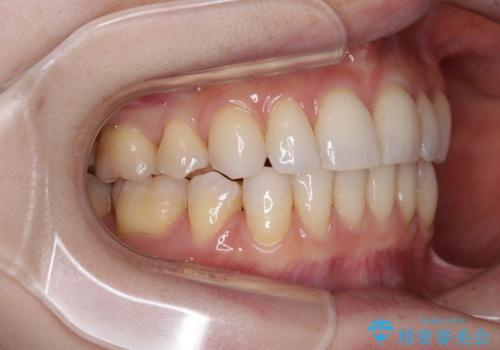

- 八重歯や前歯のデコボコを気にして来院された患者様です。

骨格的な左右差と、歯列から外れている歯が上下で左右非対称になっていることから、上下正中が歯1本分ずれている状態でした。

八重歯の改善と、上下の正中位置を極力合わせていくことを目的として、上下左右の第一小臼歯4本を抜歯し、ワイヤー装置にて矯正治療を行うこととしました。